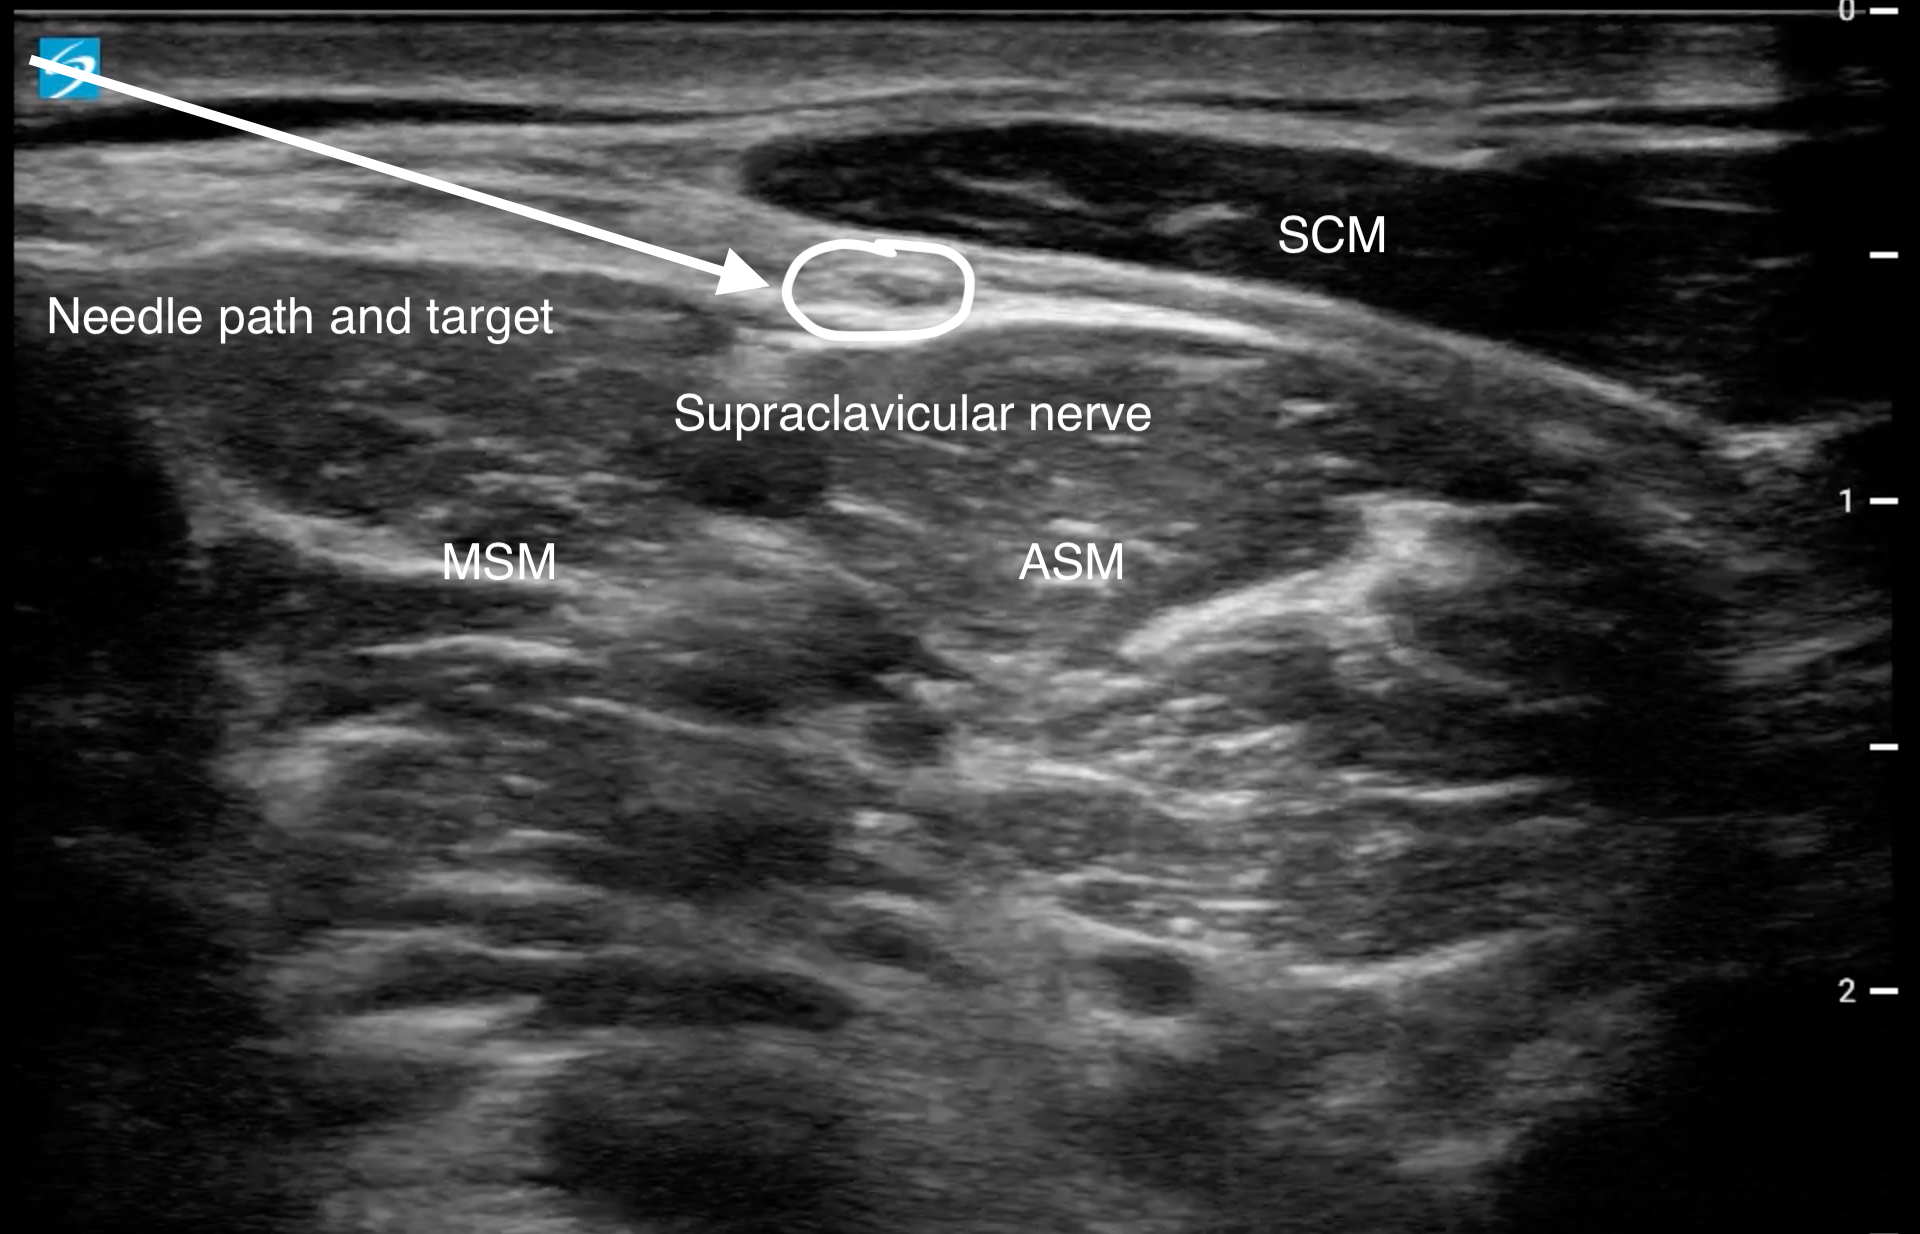

Supraclavicular nerve block

劑量2-3 ml ,Bupivacaine 0.5% or Ropivacaine 0.5%

參考胸鎖乳突肌 / 前斜角肌 / 中斜角肌 (圖片2、影片2)

圖片2Supraclavicular nerve示意圖。SCM: sternocleidomastoid muscle, ASM: anterior scalene muscle, MSM: middle scalene muscle.

定位橫向放在乳突(mastoid process)和鎖骨中段處,往鎖骨端來回掃描,確認Supraclavicular nerve的位置後由外往內入針,施打於神經週圍